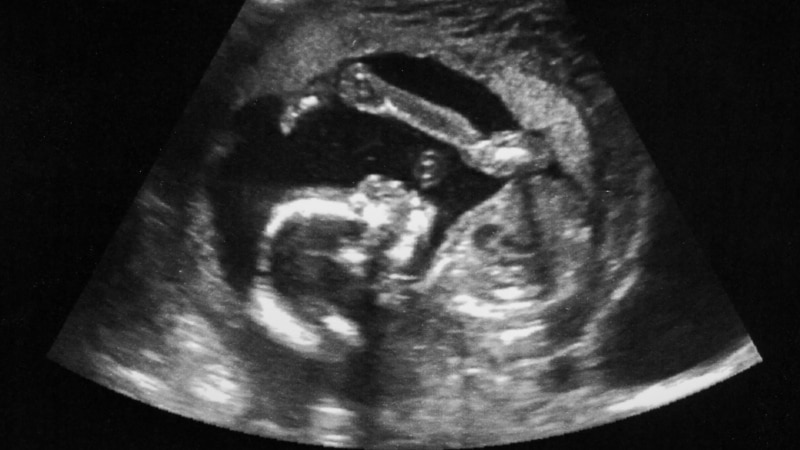

"Тянут до 12 недель, потом отказывают". Российские больницы прекращают делать аборты по госстраховке

В октябре 2025 года почти все районные больницы Забайкалья под давлением чиновников отказались от лицензии на аборт по полису обязательного